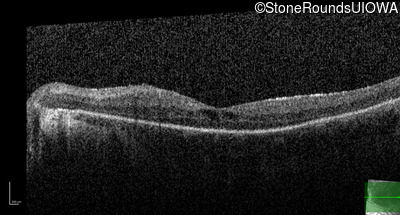

Optical Coherence Tomography - Left - 20/100 sc

Exemplar / OCT Stack